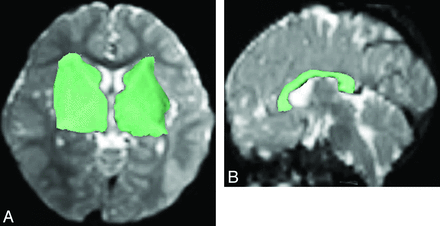

DTI data were transferred to an off-line computer equipped with an automated image registration software (Diffusion Registration Tool, release 0.4; Phillips Medical Systems, and IDL; ITT, Boulder, Colorado) to correct for eddy current and motion-related misalignment. Diffusion-weighted images, ADC, and FA maps were generated by use of Philips Research Imaging Development Environment software provided by the manufacturer. FA was calculated from the eigenvalues that were obtained by diagonalizing diffusion tensors at each voxel.8,24 Fiber tracking was performed with the use of the software, which used a line propagation technique with the assumption of the principal eigenvector indicating the orientation of axons in each voxel. Tracking was started from a seed ROI from which a line was propagated in both forward and backward directions from voxel to voxel, according to the principal eigenvector at each voxel.10 Tracking was terminated when it reached a pixel with low fractional anisotropy (FA < 0.25) and/or a predetermined trajectory curvature between 2 consecutive vectors (turning angle >30°). A lower turning angle was used in tracking termination to decrease false-positive fiber tracts and computational load.25 To reconstruct PF on 1 side, 1 investigator (A.M.W.), who is a neuroradiologist having 1 year of fellowship training in pediatric neuroradiology, 9 years of experience in practicing pediatric neuroradiology, and 5 years of experience in DTI, manually drew an ROI on an axial b = 0 section to include the ipsilateral head of the caudate nucleus, internal capsule, lentiform nucleus, external capsule, and thalamus (Fig 1A) and another ROI over the brain stem. CF within the corpus callosum were generated by placing a 2D ROI to include the corpus callosum, which was identified on the sagittal section nearest to the midline (Fig 1B). As a result, the major white matter tracts of each subject were reconstructed in 3 sessions: 2 yielding the PF and 1 yielding the CF. Quantitative results of the generated fibers, including the right and left PF, CF, and the summation of these tracts (MWT), were automatically obtained by the software,26 initiated by right-clicking with the mouse on the fibers. The results include the FA, NOP, and NOF. NOP was an arbitrary unit proportional to the volume of the generated tracts in a single reconstruction, and NOF was the number of tracts generated in that reconstruction.

Regions of interest (green shaded areas) were manually drawn on axial B0 image (A) to include the ipsilateral caudate head, internal capsule, lentiform nucleus, external capsule, and thalamus for reconstructing the PF on one side, and on sagittal B0 image (B) to include the corpus callosum for reconstructing the CF.